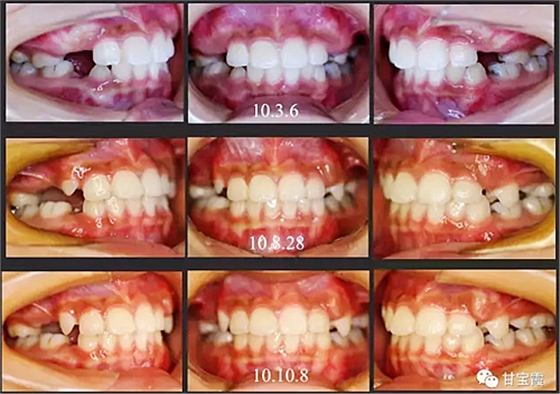

經(jīng)過我臨床檢查和X線的診斷,決定早期干預,每三個月定期復診檢查一次,并拔掉了幾個乳牙和四個恒牙,正畸專業(yè)叫序列拔牙。

經(jīng)過三年零九個月的看護,最終戴上了固定矯治器,但是大家不難發(fā)現(xiàn),孩子的牙齒已經(jīng)排齊,上下中線也基本對齊,面型也好看多了,這樣矯正就變得簡單,療程自然縮短,孩子也不遭罪了。